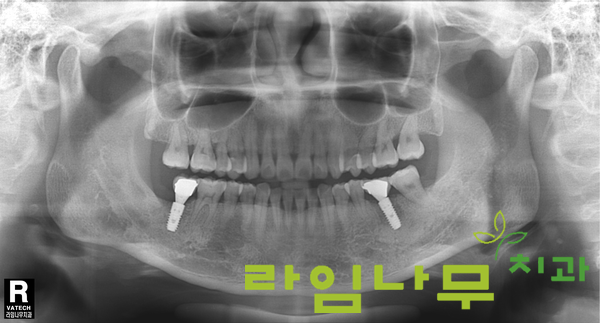

재수술 한 곳뿐만 아니라 전체적으로 치조골의 상태가 좋지 않으시기 때문에 임플란트가 고정될 때까지 각별한 관리를 당부드렸는데요,

6개월 뒤 X-ray 촬영으로 확인해보니 치조골이 아주 잘 차올랐고, 임플란트도 뼈와 잘 융합됨이 확인되었습니다.